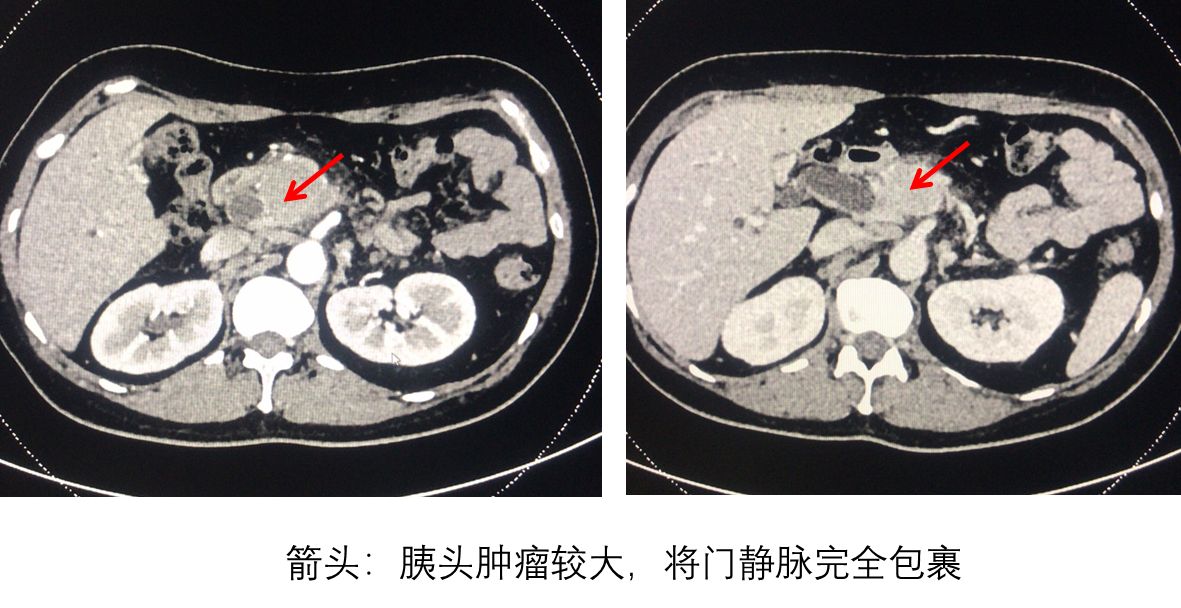

患者,中年女性,因“皮肤巩膜黄染进行性加重”就诊于多家医院,完善CT等检查均提示为胰头癌、门静脉受侵严重受压变形,癌栓形成。由于肿瘤侵犯门静脉并导致门静脉严重受压变形,门静脉完全被包裹,多家医院均告诉患者及家属手术难度大,风险极高,难以完成根治性手术切除。这对于原本平静的家庭如同晴天霹雳,患者及家属都难以接受。后经多番打听和考虑,患者及家属慕名找到厦门大学附属翔安医院肝胆外科主任李文岗教授,以求更好的治疗。

李文岗教授仔细了解患者情况,认真审阅患者的相关检查后,考虑诊断为“梗阻性黄疸:胰头癌并门静脉侵犯”。由于肿瘤非常大,侵犯范围较广,门静脉被肿瘤完全包裹,手术难度非常大,手术风险非常高。但是他充分考虑患者及家属心情后,还是决定为患者行根治性手术治疗。

患者入院后,肝胆外科高度重视,给患者再次完善了上腹部增强CT以充分评估肿瘤的可切除性,制定手术方案:胰十二指肠切除+门静脉人工血管置换术。

术中探查:胰头肿瘤非常大,侵犯了门静脉;下腔静脉、左肾静脉受压变窄,下腔静脉和腹主动脉之间多发肿大淋巴结,门静脉完全被肿瘤包裹。